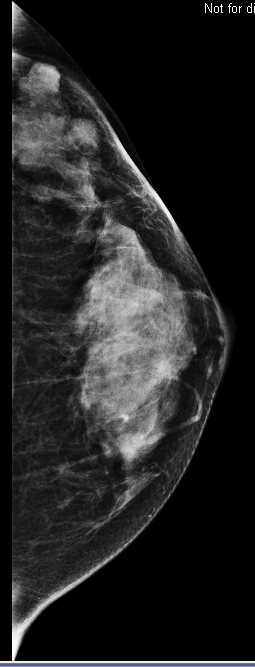

A postmenopausal woman who has previously been treated for contralater...

Read More